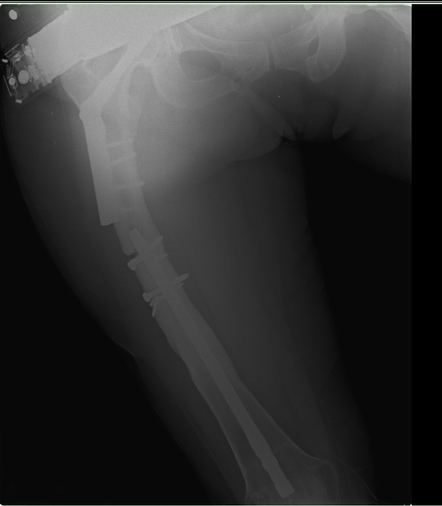

Хочется услышать ваше мнение. Пациентка 48 лет, без вредных привычек,

получила свежую травму (с\3 диафиза правого бедра) при падении с лестницы.

Ранее (8 лет назад) была множественная травма, на бедре–  перелом с\3,

выполнен остеосинтез DFN  Synthes (в др. ЛПУ). Перелом диафиза

консолидировался очень медленно, от реостеосинтеза категорически

отказывалась, в результате к 2 годам наступило сращение. Беспокоили боли

при нагрузке, на рентгенограммах–  зона разрежения вокруг кончика

(проксимального) стержня и проксимальных винтов, согласилась лишь на

удаление дистальных винтов для динамизации стержня. Пациентка пропала из

поля зрения. Затем спустя 2 года при падении получает чрезвертельный

перелом, выполнен остеосинтез бедренным винтом ( DHS ).

Планирую удаление имплантов (кроме проволоки), рассверливание

костно-мозгового канала (сейчас стоит гвоздь 10 мм, попытаюсь

рассверлить до 14-15 диаметра, чтобы поставить 12 мм или 13 мм гвоздь),

внутрикостный остеосинтез блокированным стержнем (динамически).